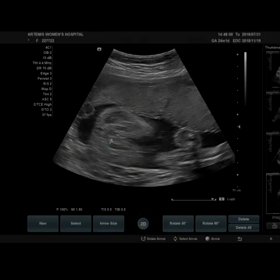

妊婦検診 13w0d 初の3D、4D動画